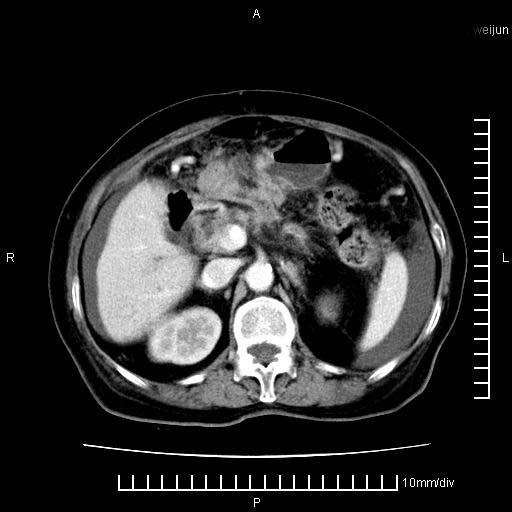

标题: CT28280:腹部增强:女性,80岁

上腹疼痛月余,外院核磁诊断胰腺癌。现临床示右下腹可明显触及包块,可片子上怎么没有看到?

1.胰腺颈体部癌。

胰腺体部癌累及周围器官,腹膜、粘连

1。胰腺ca伴腹膜腔转移

2。肝左叶低密度灶,考虑转移可能

支持胰腺癌肝内转移,腹水改变。

胰腺结构模糊,胰尾部见囊性包块,周围脂肪密度增高,左肾前筋膜增厚,胸水、腹水。不符合胰腺ca伴腹膜腔转移。考虑胰腺炎伴假性囊肿形成、胸腹腔积液。

右肾盂囊肿。

1、考虑胰腺癌伴腹膜腔转移,胸腹水。

1)考虑胰腺癌并胰腺假性囊肿形成。2)肝内低密度灶,不排除转移。3)右肾盂积水。4)腹水。5)右侧胸腔积液并右肺下叶部分膨胀不全。

考虑胰腺ca伴腹膜腔转移、肝左叶转移、右肾积水。右胸腔积液。